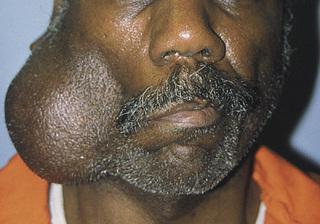

Tender swelling of the submandibular gland. An associated low-grade fever and trismus may be present.

sialadenitis